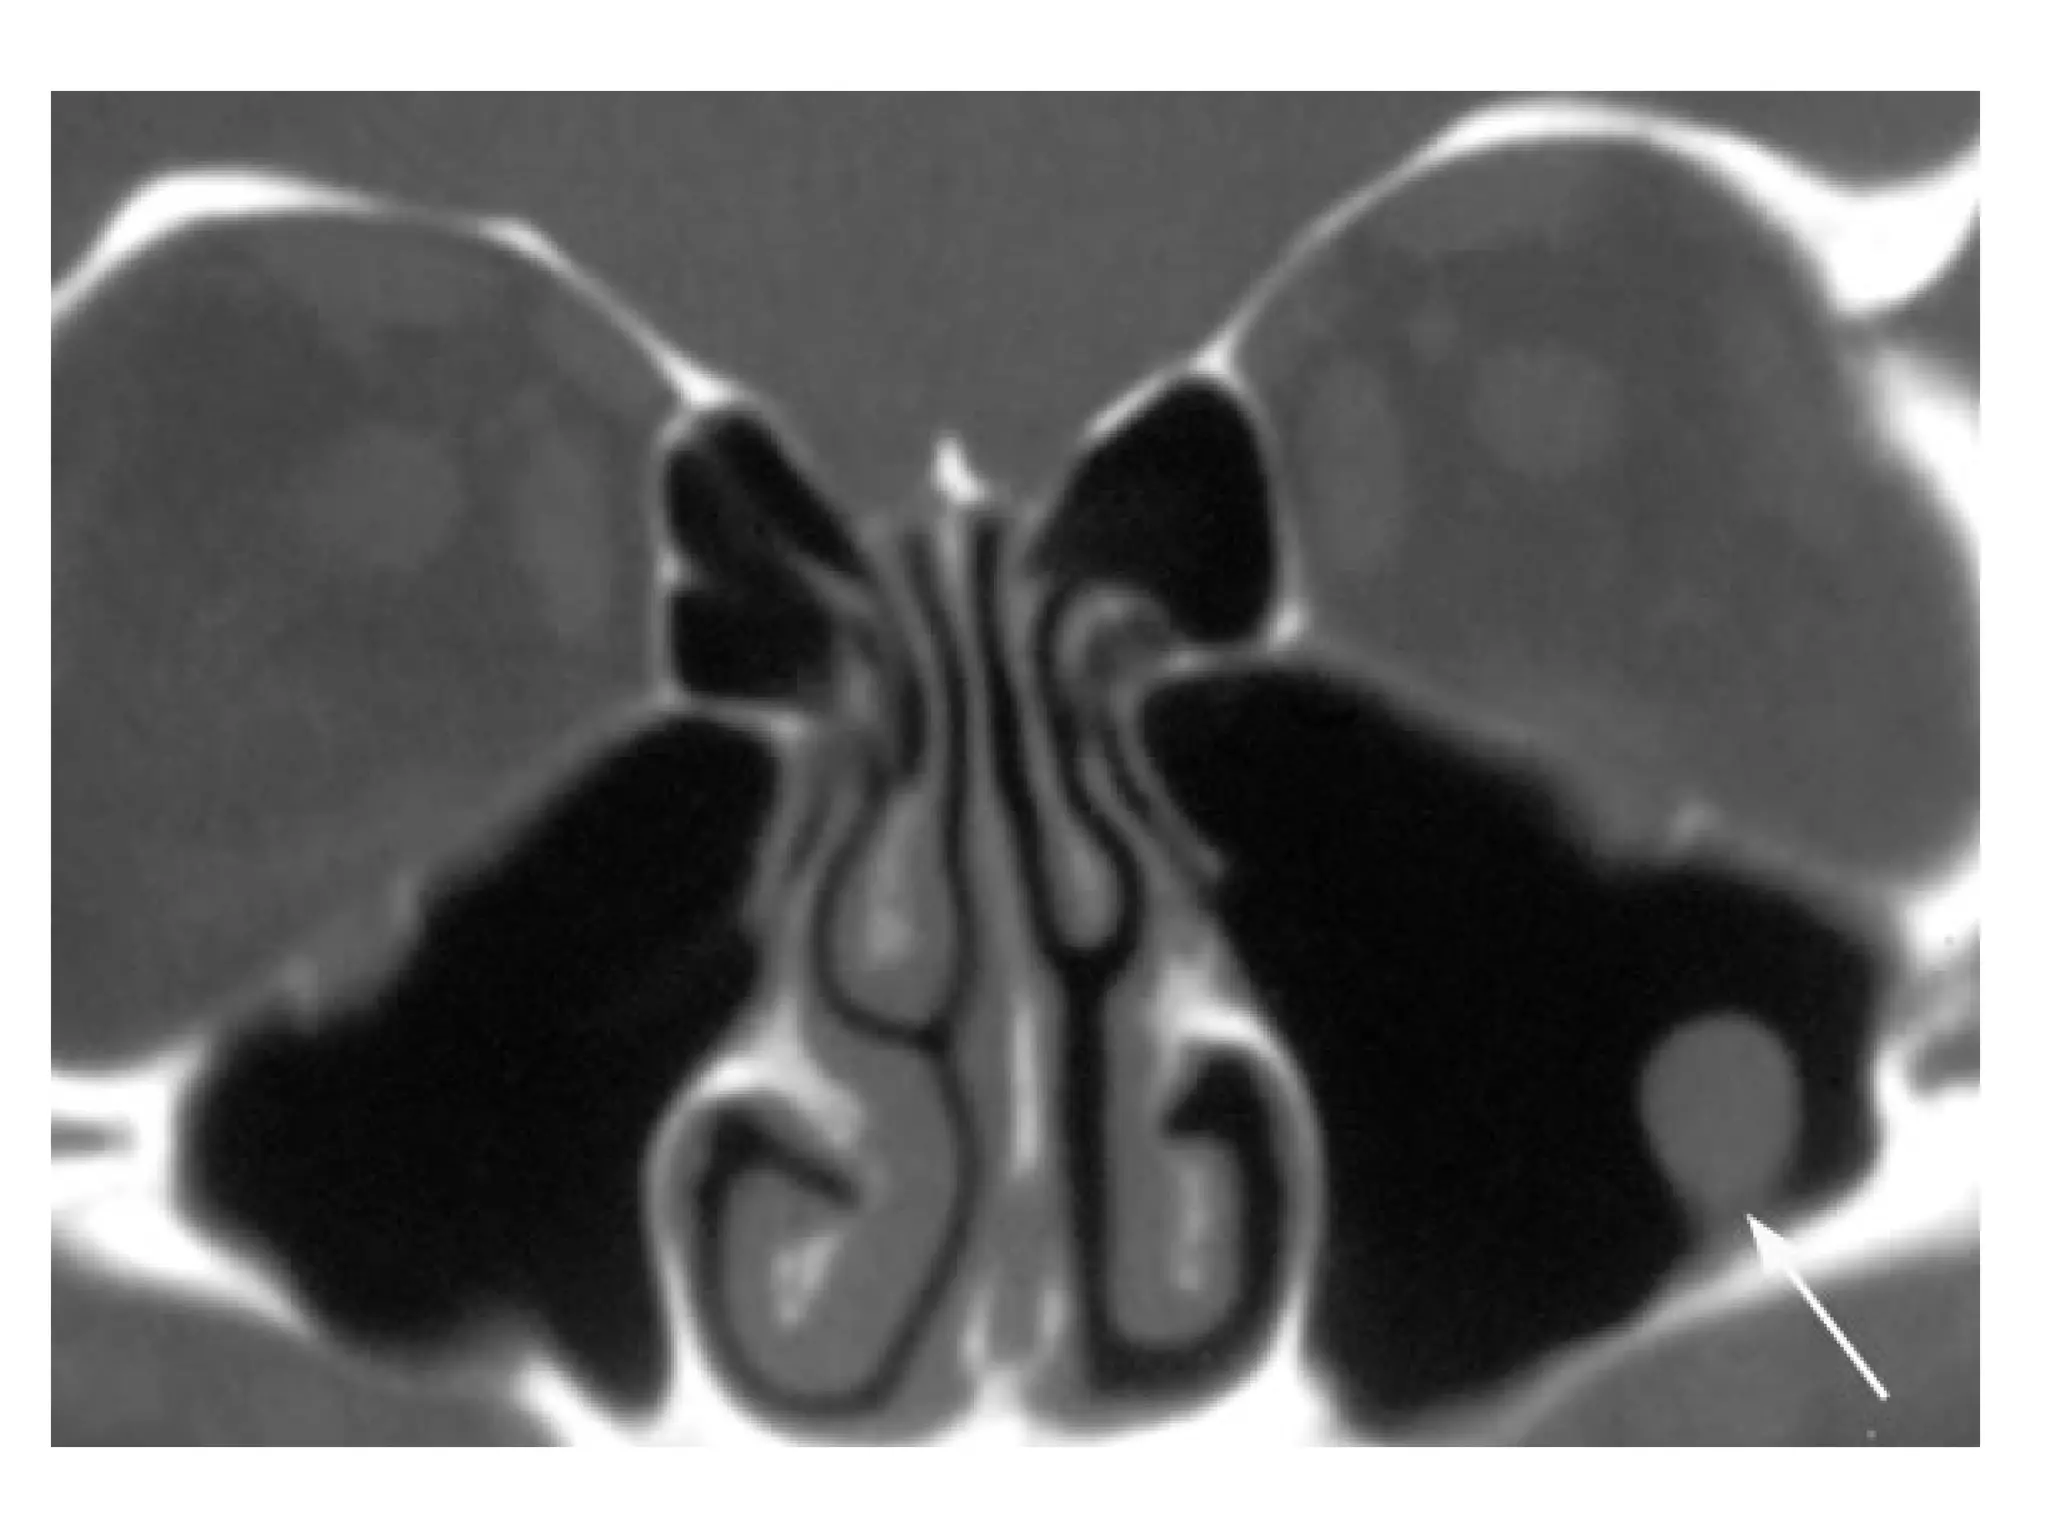

Mucocele of the sphenoid and ethmoid sinuses

Axial unenhanced CT image shows opacification of the left sphenoid

sinus due to a mass (arrow) causing slight expansion of the sinus,

some parts of the sinus wall are thin and some are thick